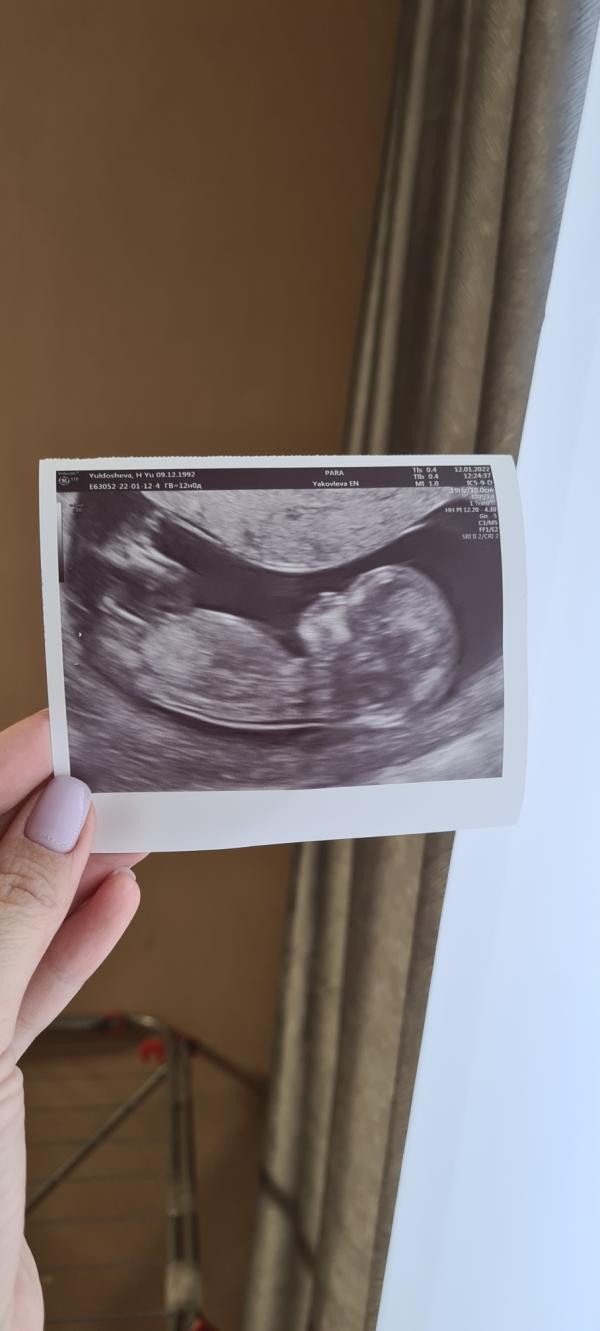

Девочки хоть с первого скрининга прошел месяц ,решила сегодня поделитесь с вами нашей первой фотографией))пол нам не сказали, может кто то что нибудь рассмотрит?)

Жаль тут нельзя выложить видео,я бы показала как человечек махал нам ручкой🙋♂️

Предположу девочку) прост интуитивно)

Кажется у вас очень развитая интуиция, сегодня сходили на Узи сказали девочка 🌸

Мальчик